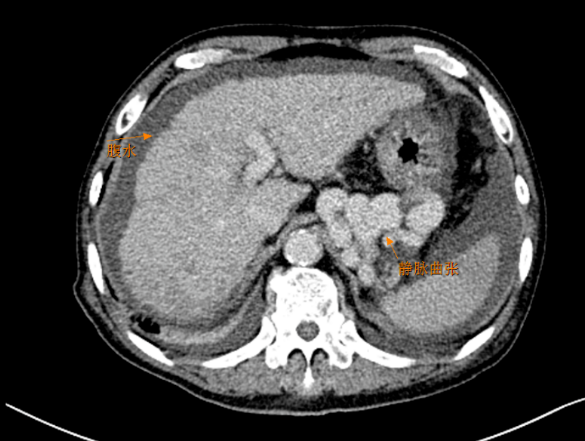

2月下旬,穆先生(化名)突发呕血,在上级医院治疗后返家,然而,不到一周的时间,穆先生再次发生呕血、便血,经120紧急送至北京燕化医院,经问诊及详细检查,患者患有肝硬化,此次是因食管胃底静脉曲张破裂,导致急性消化道大出血。入院时,患者血压骤降,血色素低至68,处于休克边缘,生命危在旦夕。普外科医疗团队迅速响应,在陈安良主任的带领下,即刻启动紧急救治方案。

由于患者病情危急且复杂,传统治疗难以快速止血,经过多学科的全面评估与深入探讨,医疗团队决定采用TIPS介入技术,通过搭桥的方法缓解门静脉高压,从根源上解决出血问题。这种创新的手术方式,通过搭建血管旁路,有效降低门静脉压力,减少食管胃底曲张静脉破裂出血风险,具有创伤小、恢复快等优势,为患者带来了生机。

TIPS(经颈静脉肝内门体分流术)门静脉高压支架手术是一种治疗门静脉高压相关并发症的重要介入手段,是以微创的方式达到治疗门脉高压及胃食管静脉曲张破裂出血的目的,这项技术被业内誉为“介入手术皇冠上的明珠”。相对传统外科手术创伤小、恢复快,对于不适合外科手术或者病情危急的门静脉高压患者来说,TIPS门静脉高压支架手术是一个不错的选择。早期TIPS门静脉高压支架手术可以显著提高患者的生存率,降低再出血、顽固性胸腹水等发生率,减轻患者和社会的经济负担。